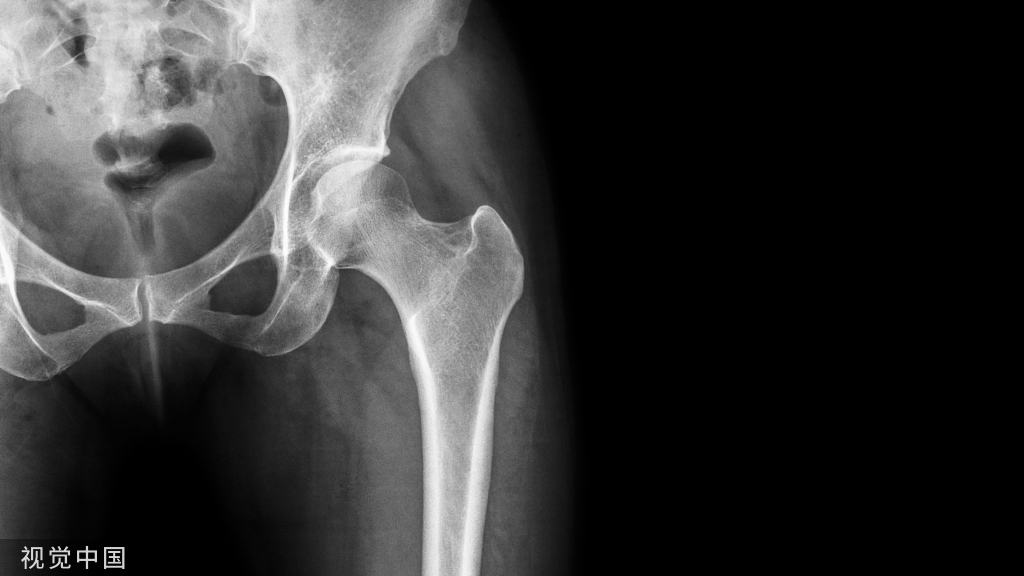

锁骨骨折合并同侧肩锁关节脱位是临床较为少见的损伤,伤后锁骨远端骨块相对游离,合并的肩锁关节脱位可能移位不明显,容易漏诊。

单纯锁骨骨折或单纯肩锁关节脱位均是临床非常常见的损伤,锁骨骨折占全身骨折的2.6%-4%,肩锁关节脱位占肩胛带损伤的12%-35%;但两者的合并伤较为少见。